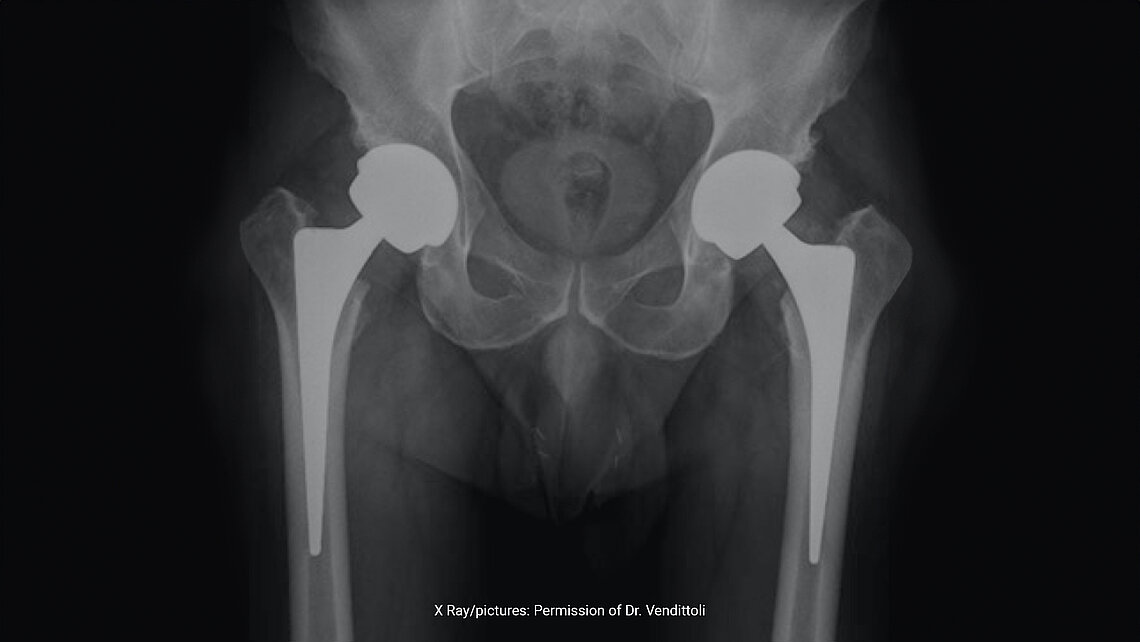

98.7% Survivorship and High Patient Satisfaction with LDH Monobloc Ceramic-on-Ceramic Systems after 10 Years

High implant survivorship: After a minimum of ten years, the implant survivorship rate stands at an impressive 98.7%, with very low revision rates (1.3%). The reasons for revisions included issues such as trauma and infection. No dislocations or ceramic implant fractures were observed, highlighting the reliability and stability of the LDH CoC bearings.

The study shows that the utilization of large-diameter head BIOLOX®delta CoC bearings like MAXERA® in THA offers remarkable long-term benefits, including enhanced joint stability and movement, without the common complications associated with smaller diameter or different material bearings.

X Ray/pictures: Permission of Dr. Vendittoli